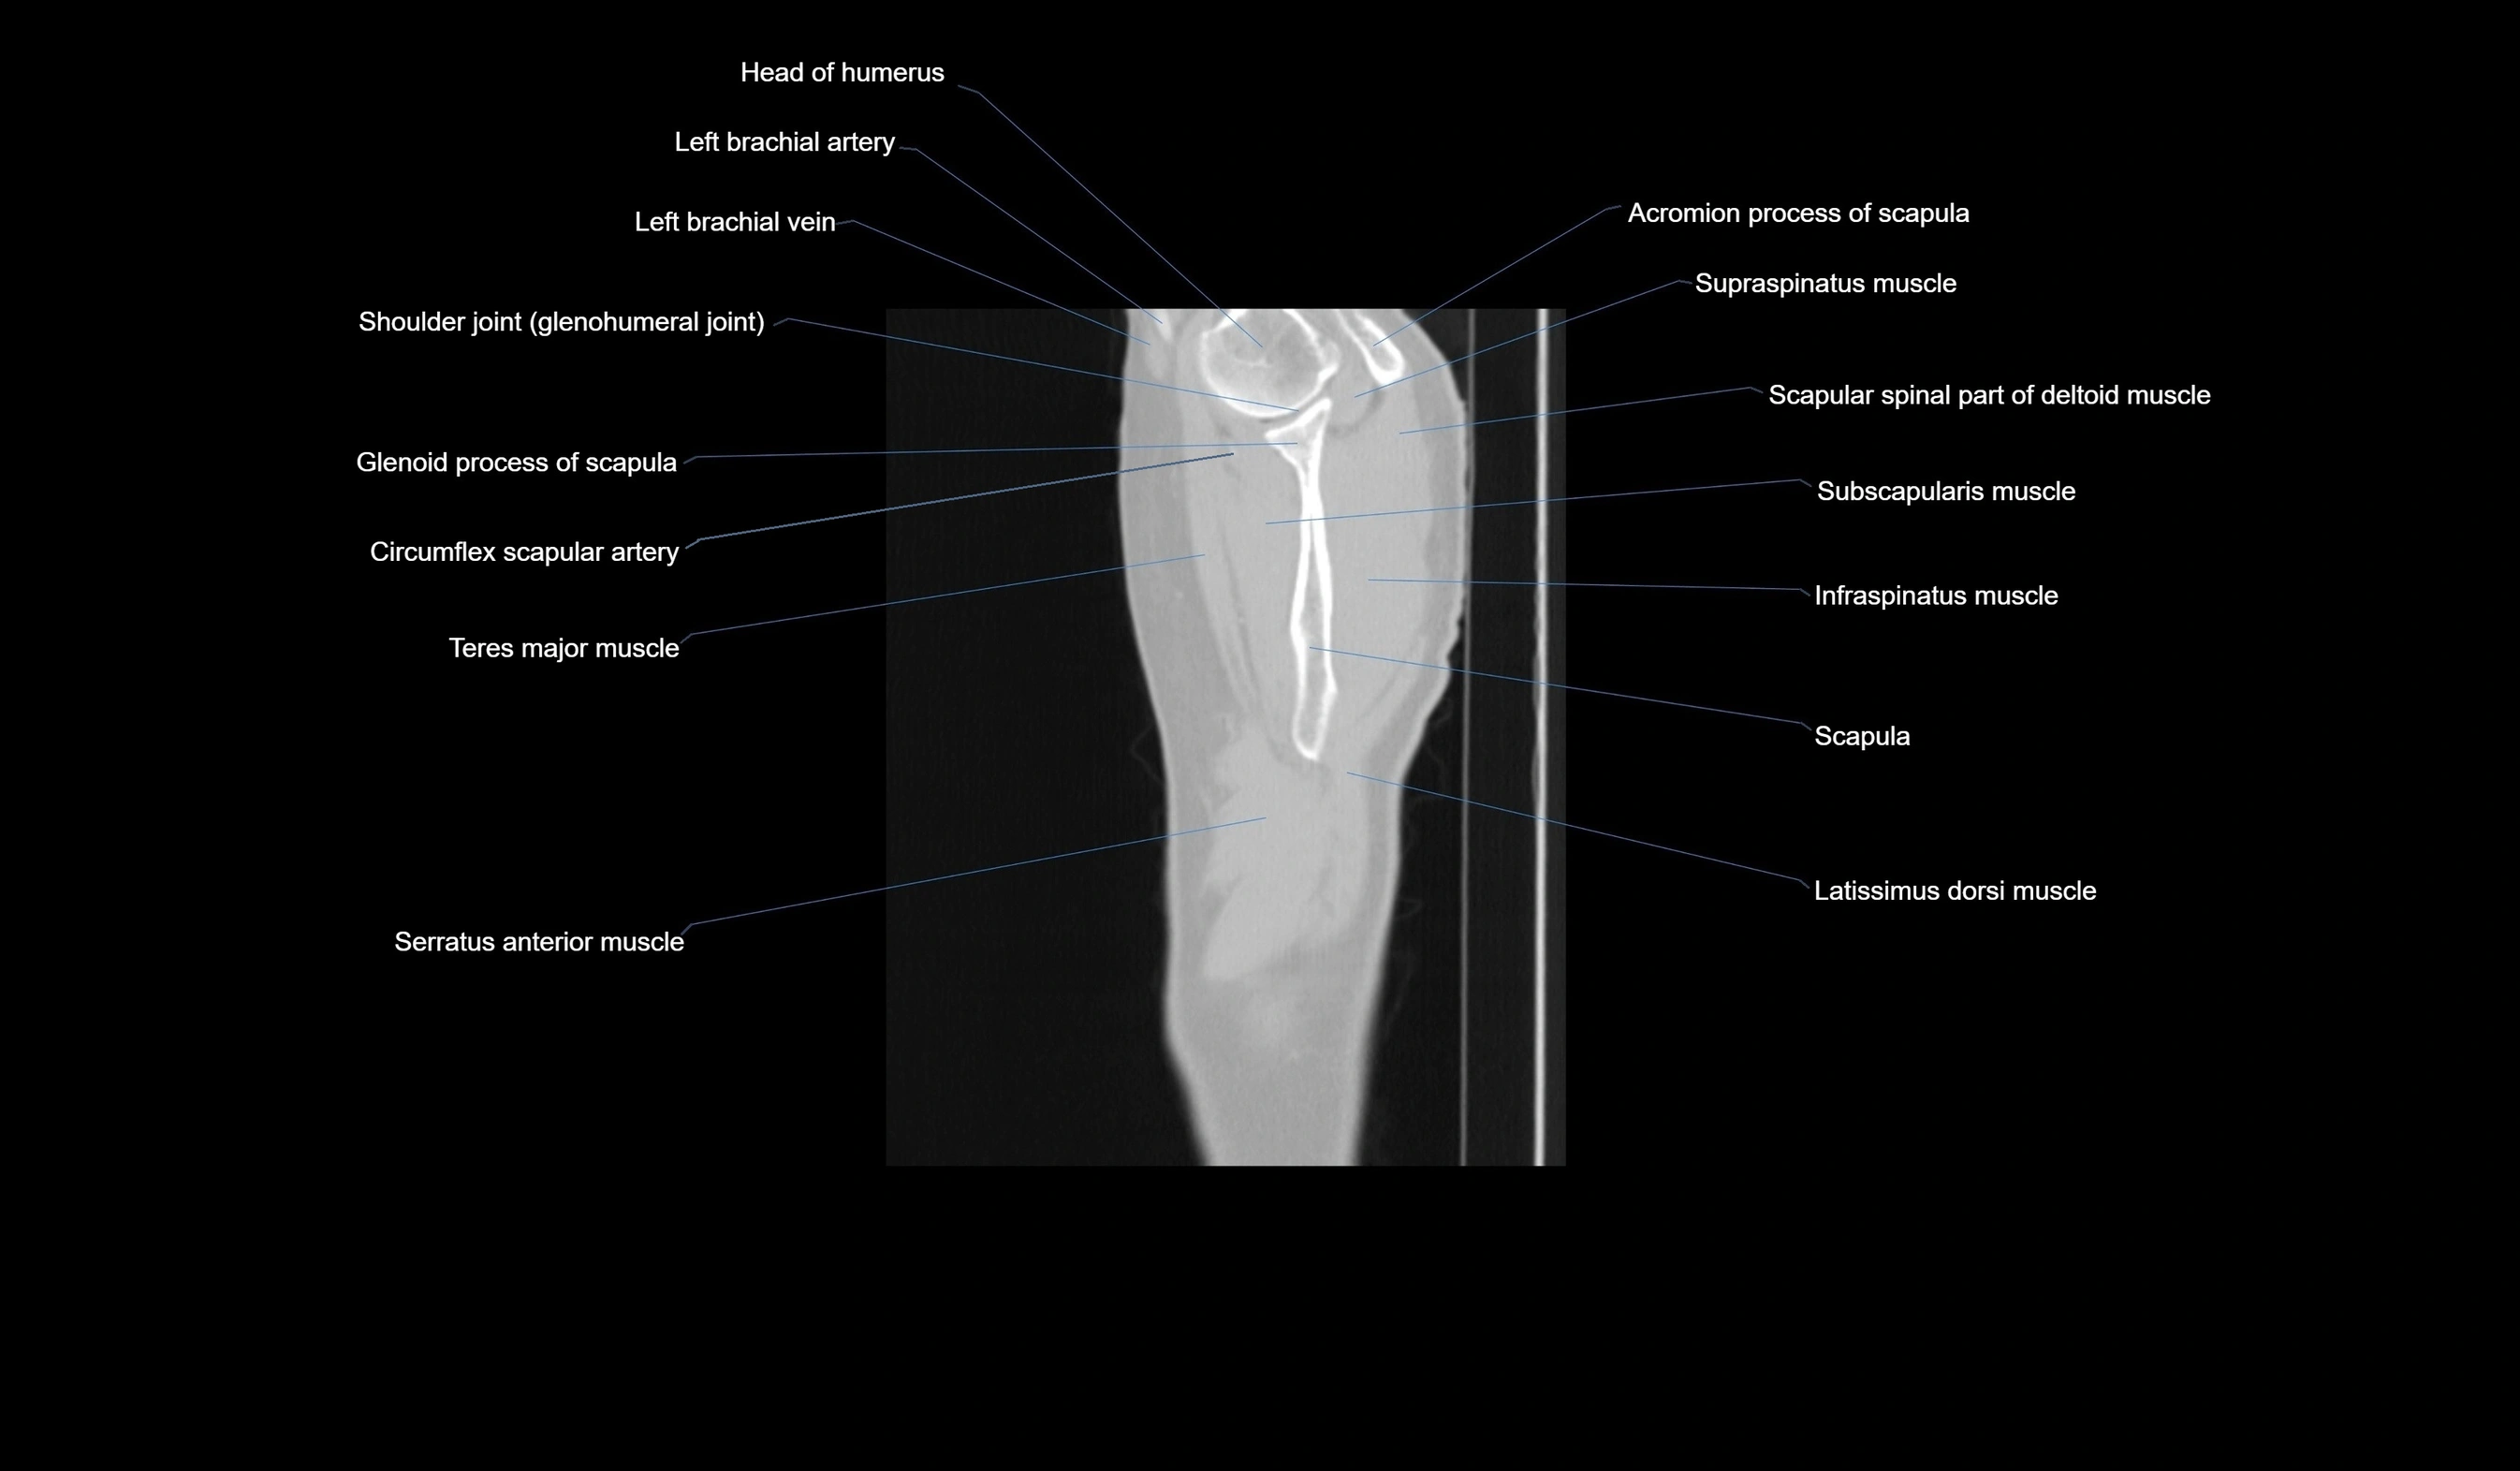

CT images